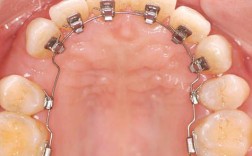

(图片来源网络,侵删) -